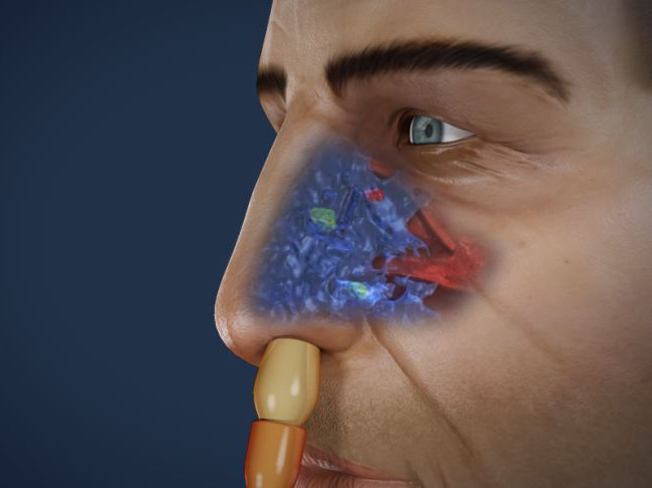

홍보, 학회 발표, 수술 교육, 의학 제품 소개와 관련한 영상을 3D로 제작하여 제공해드립니다.

제작범위 : 신체 전신, 뼈대, 장기, 혈관 등 사람, 동물의 모든 표현이 가능하며, 수술과 관련한 도구 제작도 가능합니다.